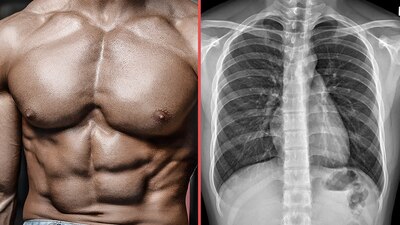

El hombre fue intervenido tras tomarle una radiografía que mostró obstrucción intestinal

Los vómitos, dolores estomacales y malestar generalizado hicieron que los médicos ordenaran hacerle una radiografía que reveló una obstrucción intestinal que, de inmediato, lo puso en la antesala de una cirugía para extraerle los materiales que lo estaban dañando internamente.

Tras la intervención, el hombre mejoró y se le praticó una radiografía más para corroborar que todos los objetos habían sido removidos de su estómago.